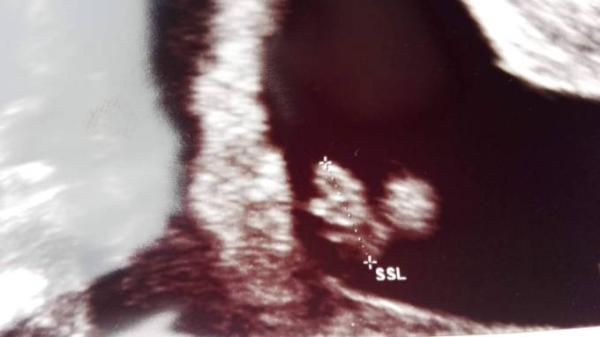

Hallo ihr Lieben. Ich reihe mich mal mit ein und stelle mich gern vor. Ich bin 32 und habe bereits einen 3jährigen Sohn. Nach der Nachricht PCO und einem dreiviertel Jahr erfolglosen Versuchens durfte ich mir heute den 1.3. als ET einschreiben lassen. Nun hat meine Ärztin aber heute zu mir gesagt dass meine Fruchthöhle viel zu groß wäre. Größe Kind ist aber normal und Herzschlag auch sichtbar. Ein Zwilling ist noch nicht erkennbar aber nicht ausgeschlossen. Bissl Sorge habe ich mit der Krankengeschichte allerdings schon... Vielleicht hat da jemand von euch schon Vorerfahrung?

Bild zu Auch dabei und Fruchthöhle - Forum für März - Mamis